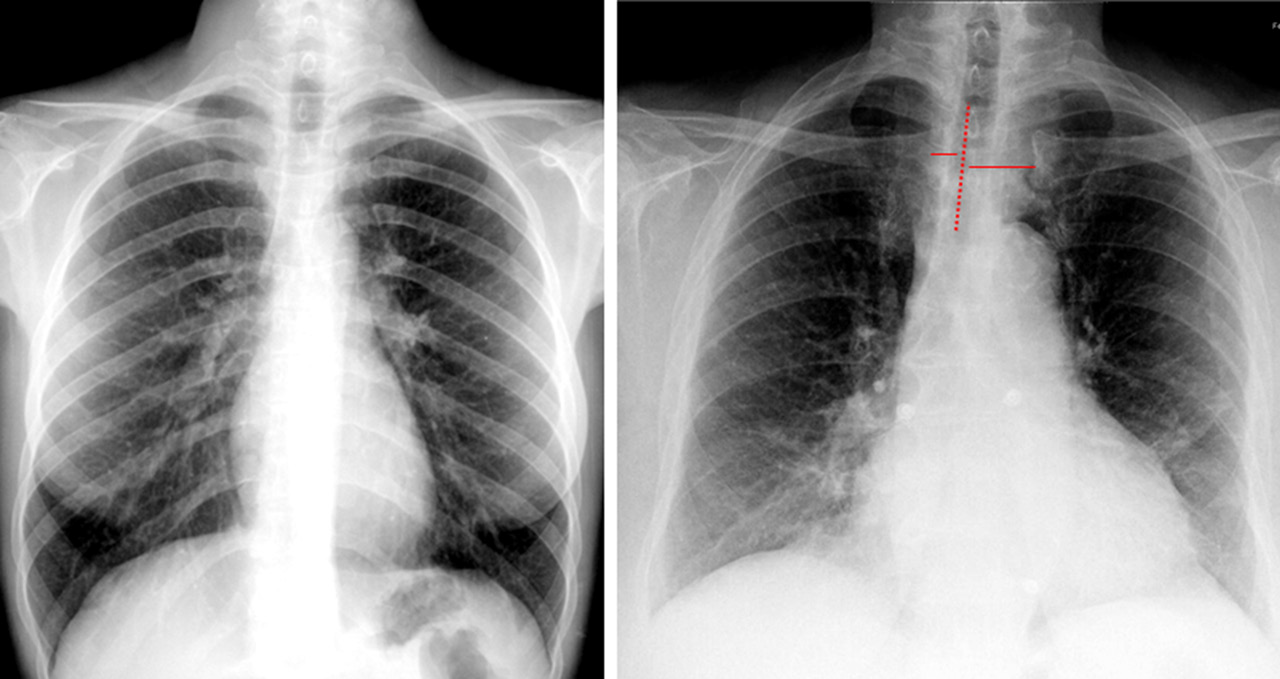

Índice cardio torácico: A+B/C

Clasificación del aumento de la silueta cardíaca:

➢ Grado 1: 0.51-0.55

➢ Grado 2: 0.56-0.60

➢ Grado 3: 0.61-0.65

➢ Grado 4: >0.65

NOTA: El diagnostico de cardiomegalia debe realizarse por ecocardiograma, la radiografía nos da un indicio al evidenciarse un aumento de la silueta cardíaca.